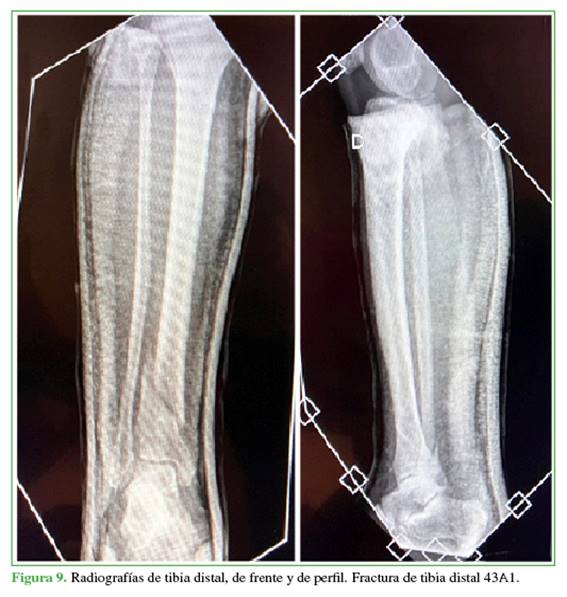

Se introduce el clavo de la longitud planificada bajo control radioscópico y, por último, se acerroja a distal con la guía externa y a proximal, a manos libres (Figuras 8-10).

Durante 2022, se colocó este implante en 15 pacientes: 13 hombres y 2 mujeres, con una edad que oscilaba entre 31 y 86 años (promedio 51.5). Las causas de la lesión habían sido: accidente de moto (6 casos), caída de altura (8 casos) y una complicación de un procedimiento quirúrgico previo (1 caso). Las fracturas se clasificaron según la AO Foundation/Orthopaedic Trauma Association (AO/OTA): 11 eran 43A1; 2, 43A2; una, 42A1 y una, 42A3. Cuatro de estas fracturas eran expuestas, 3 Gustilo IIIA y otra IIIB, tratadas inicialmente con desbridamiento quirúrgico, colocación de terapia de presión negativa y fijador externo en la urgencia. A las 48 horas, se las convirtió a fijación interna con clavo retrógrado y colgajo libre lateral de muslo en el caso de la fractura IIIB. El peroné fue estabilizado en 10 pacientes (6 con placa y tornillos, 4 mediante un clavo endomedular elástico).